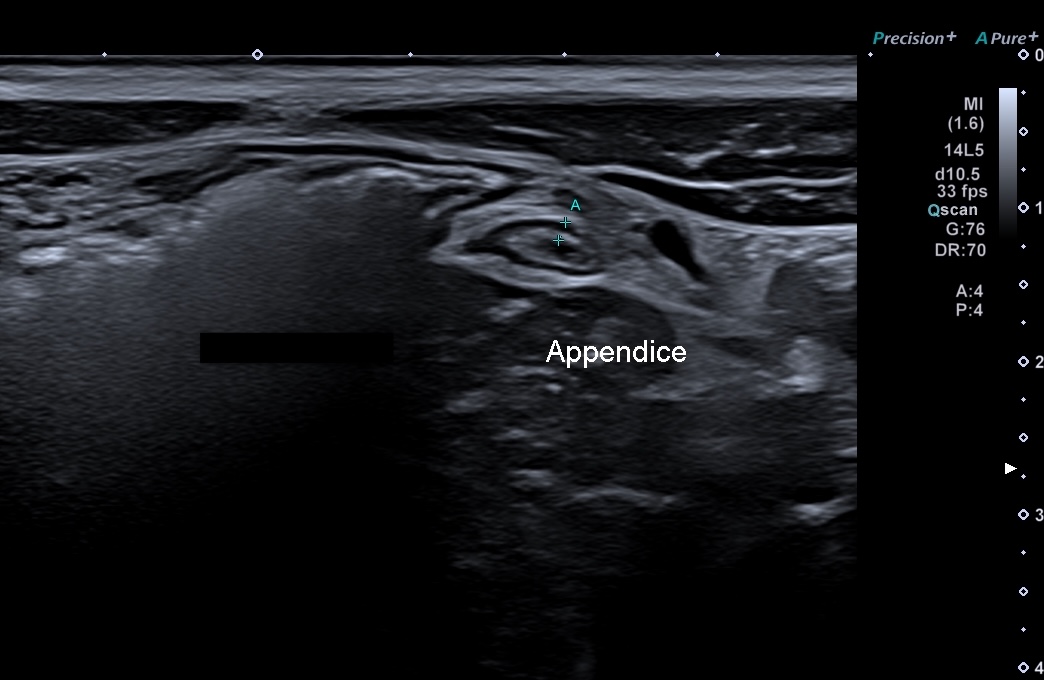

aspect en "w" lié aux deux berges de la valvule (généralement hyperéchogènes) rentrant dans le caecum.

Là encore les 5 couches sont très fines

Aspect de tube très fin relié au caecum,

Pas de péristaltisme propre

Souvent posé sur le psoas.

On le voit difficilement et pas toujours